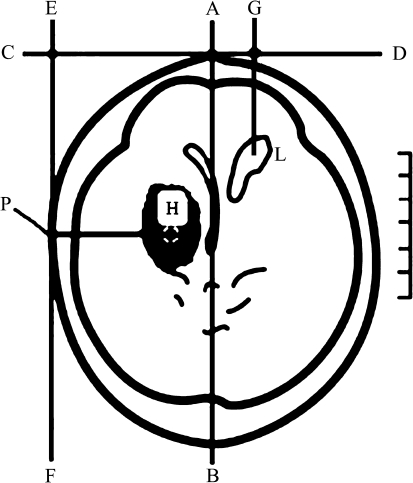

All operations were performed under local anesthesia and intravenous sedation unless the patient was already intubated for medical or neurological indications independent of the procedure. Stereotactic aspiration of the hematomas was performed in the acute phase between the 6th and the 24th hour after onset of stroke as required in the MISPTT protocol. First, the target points were defined according to the CT, and target points were generally chosen in the scan with the largest expansion of the hematoma and special attention was paid to stay away from important cortex function areas (Fig. 1). Puncture situs was measured and marked on the head, again avoiding main blood vessels, then a puncture needle of suitable length (type YL-1) was fixed to the operative electric drill. The puncture needle was entered to the predetermined depth, then the probe core was removed; the hematoma was withdrawn gently using a syringe (diluted with saline if blood thickened) until one-third of hematoma was removed, then a needle-like hematoma disintegrator was inserted. When no more blood could be withdrawn, the hematoma cavity was thoroughly rinsed with saline, until the saline fluid was clear.

Fig. 1.

The slice of the largest hematoma area and puncture point in the CT are illustrated. AB median sagittal line, CD precoronal line, EF lateral sagittal line, P puncture point of hematoma, H center of hematoma, G puncture point of lateral cerebral ventricle, PH puncture depth, L lateral cerebral ventricle